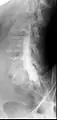

توموگرافی کامپیوتری بعد از میلوگرافی معمولی. نمایش بدون همپوشانی اغلب امکان ارزیابی مطمئن تری را فراهم می کند. تراکم بالای ماده حاجب ممکن است در صورت مخلوط نکردن کافی قبل از CT مشکل ساز باشد.